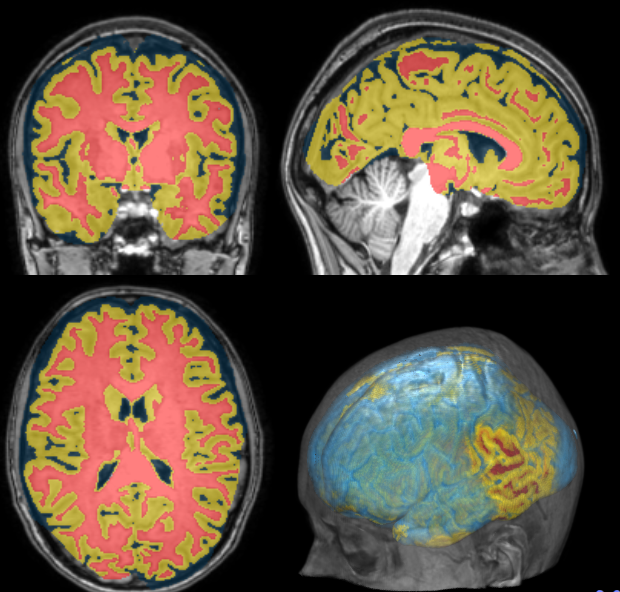

3. Segmentation (Manual, Template-based)

Segmentation

Measurements

Cortical Thickness Estimation